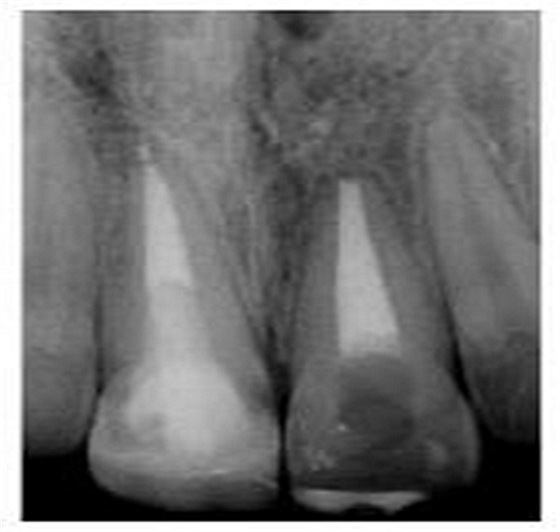

專業(yè)醫(yī)師對患者進(jìn)行了仔細(xì)檢查及診斷分析。11被診斷為冠根折伴牙髓暴露及大面積牙體缺損。21被診斷為側(cè)向移位伴冠折。檢查活動夾板在位,兩中切牙根管治療術(shù)中,氫氧化鈣根管內(nèi)封藥。11明顯變色。11用Cavit暫封,21復(fù)合樹脂充填。11腭側(cè)頸部有一折裂片。

切端則采用透明樹脂,最后使用釉質(zhì)樹脂(Amaris, VOCO, Cuxhaven, Germany)。21的樹脂修復(fù)采用類似的方式。修復(fù)初步成型,拋光,恢復(fù)干燥牙釉質(zhì)的顏色。攝片顯示樁在根管內(nèi)位置合適(圖15)。最后一次復(fù)診精修、拋光充填體,完成治療。